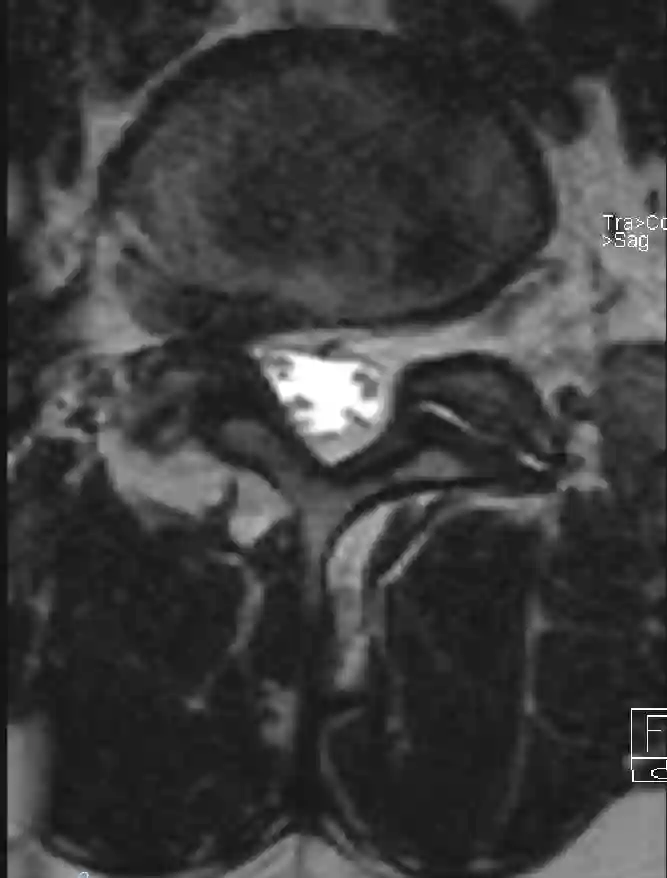

Axiales T2 MRT intraforaminaler Bandscheibenvorfall

Axiale T2 Sequenz eines Patienten mit einem intraforaminalen Bandscheibenvorfall auf der rechten Seite.